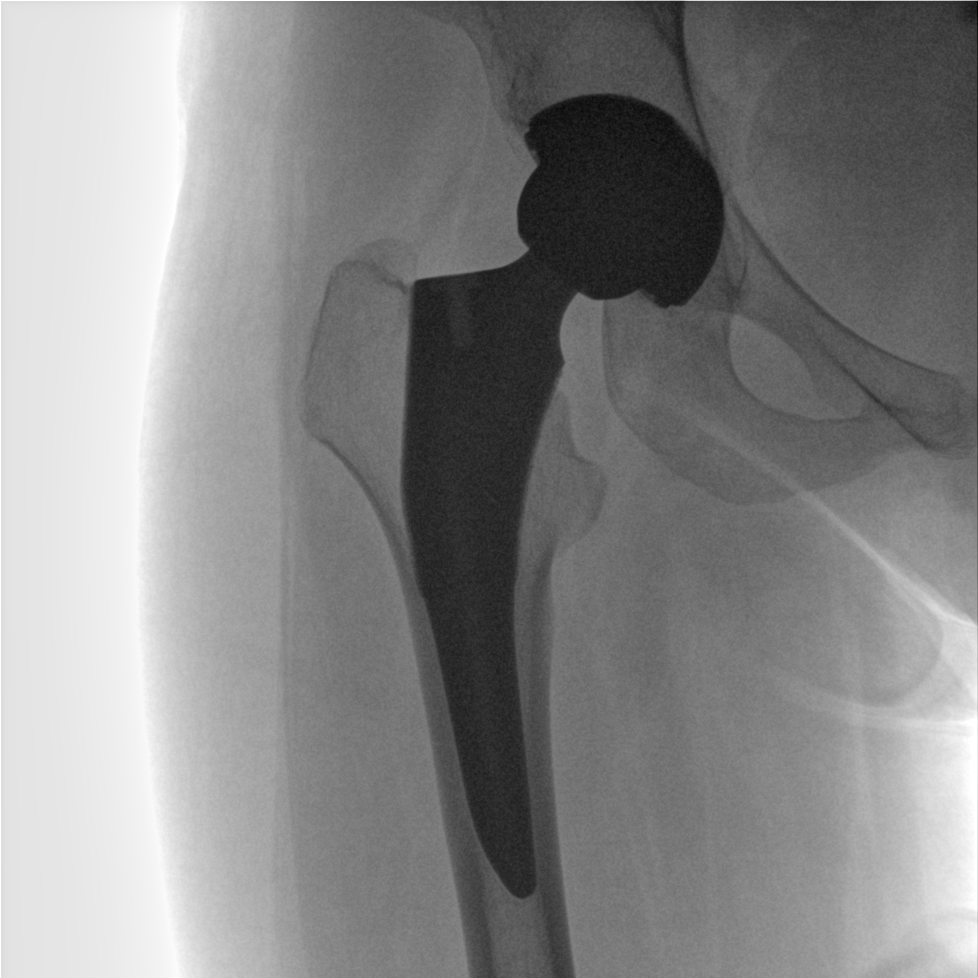

提供更大的術(shù)中三維成像視野,采集更多圖像信息,可一次拍全全段頸椎、全段腰椎、七節胸椎、雙側骶髂關(guān)節、股骨頭及單側盆骨。